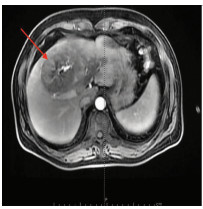

Anti-PD-1 monoclonal antibody combined with apatinib in treatment of rare primary squamous cell carcinoma of the liver: A case report

Yuchen FEI, Donglai LYU

2021, 37(3): 670-672. DOI: 10.3969/j.issn.1001-5256.2021.03.032

Abstract(870) HTML (228) PDF (2972KB)(48)

Abstract: